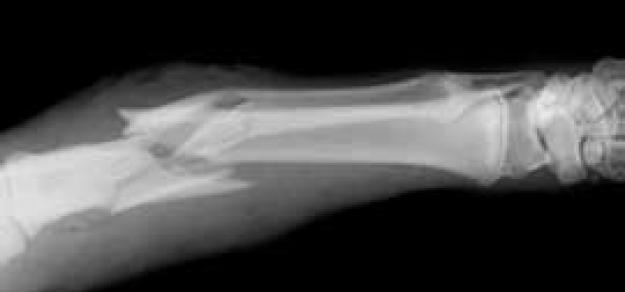

Investigación multinacional del riesgo de fractura con el uso de antidepresivos por clase, fármaco e indicación.

El riesgo de fractura para los pacientes puede reducirse seleccionando paroxetina, un ISRS con menor riesgo que el citalopram, la venlafaxina sobre la duloxetina y la amitriptilina ATC sobre la imipramina o la doxepina. Existe incertidumbre sobre el riesgo asociado con los antidepresivos atípicos. J Am Geriatr Soc 17 de marzo de 2020